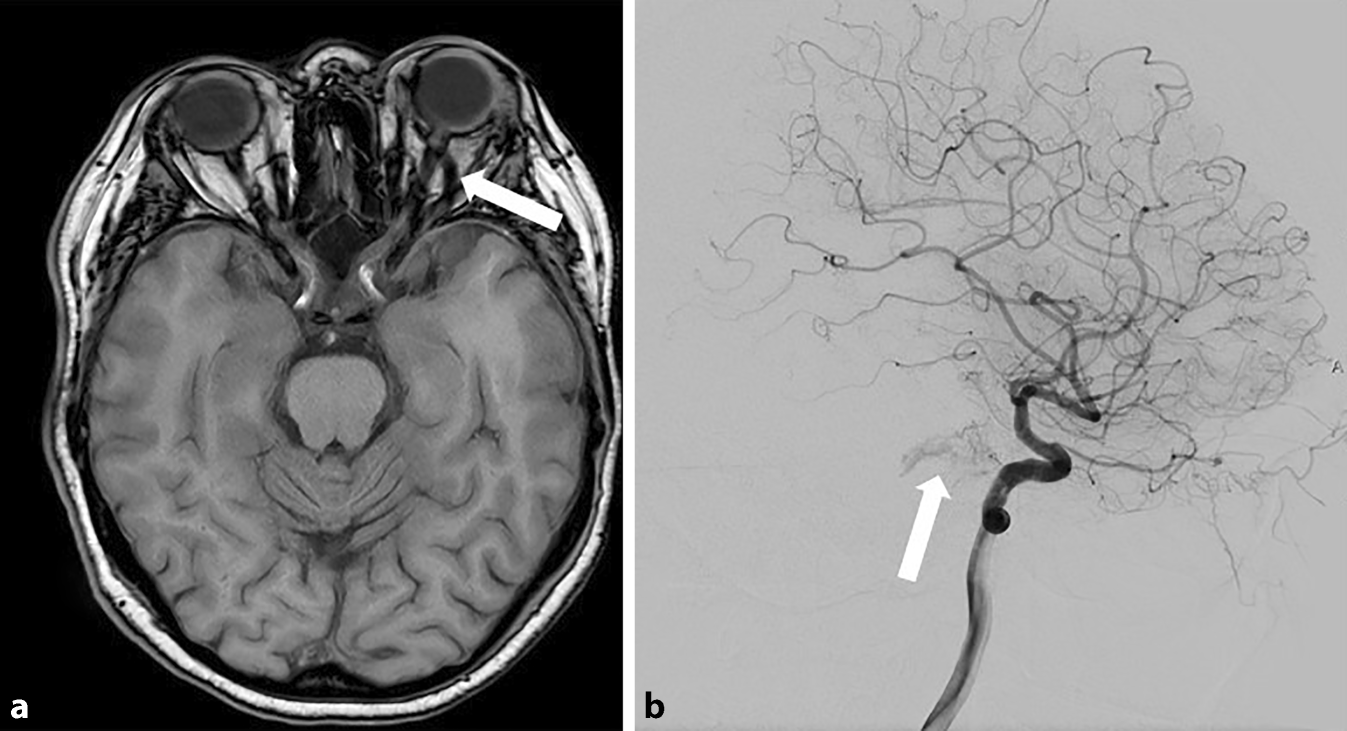

Carotis sinus cavernosus fistel. Ihren Ästen und Sinus cavernosus. Direkte Shuntverbindung zwischen der Arteria carotis interna und des Sinus cavernosus. A Angiographie der Arteria carotis communis in seitlichem Strahlengang.

Anhand der Barrow Klassifikation werden Carotis-Cavernosus Fisteln in 4 Gruppen eingeteilt. Das Coiling bezeichnet ein neurochirurgisches angiographisch gestütztes Verfahren zur endovaskulären Embolisation zerebraler Aneurysmen und arteriovenöser Fisteln Carotis-Sinus-cavernosus-Fistel. Mehr zu Symptomen Diagnose Behandlung Komplikationen Ursachen und Prognose lesen.

Eine spezielle Komplikation nach einem Schädel-Hirn-Trauma insbesondere nach Schädelbasisverletzung stellt die Carotis-sinus-cavernosus-Fistel dar. Carotis mit vollständiger Rückbildung der Symptome in einem Fall. Typisch sind gestaute episklerale Venen bei wechselnd ausgeprägter Protrusio bulbi.

Carotis interna im Sinus cavernosus verletzt fließt das Blut der Arterie in den venösen Sinus. Traumatisch frontobasale Schädelbasisfraktur Aneurysmaruptur A.